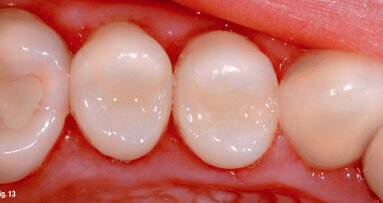

Additionally, semi-sequential distalisation of the premolars and canines was planned (Fig. 7). During semisequential distalisation, small gaps are initially created between the premolars to allow the aligner to better grip and move these teeth. After molar distalisation had been completed, the distaliser was kept in place to anchor the molars until the premolars had been fully distalised, preventing unwanted mesial drift. It is important to note that teeth #16 and 26, which were connected to the distaliser, could only undergo bodily distalisation. The rigid anchorage does not permit tipping and rotational movements of the first molars. Therefore, such movements of the first molars should be avoided in the ClinCheck planning. The aligner shells on teeth #16 and 26 were additionally equipped with horizontal attachments.